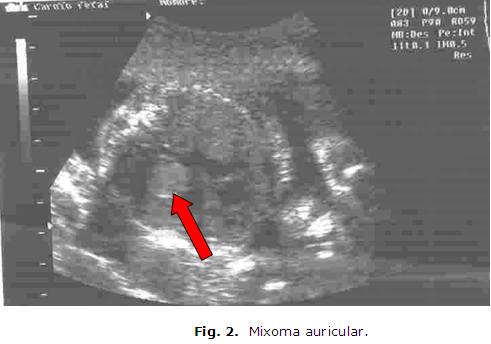

Con riesgo genético incrementado por padecer de Neurofibromatosis, por lo que se remitió al Centro Provincial de Genética Médica de Pinar del Río a las 24,4 semanas de embarazo y se realiza USG. El resultado fue: Biometría Fetal que concuerda con tiempo de gestación, líquido amniótico disminuido y en la ecocardiografía fetal, a nivel de la aurícula izquierda se observa imagen ecogénica de aspecto tumoral de 10mm, que impresiona un mixoma auricular, en la pared libre del ventrículo izquierdo, imagen de 7mm, con aumento de la ecogenicidad que impresiona se corresponde con un fibroma. (Figura 1), (Figura 2), (Figura 3)

Los mixomas suelen ser

únicos y en el 75% de los casos aparecen en la aurícula

izquierda, la zona de origen habitual es